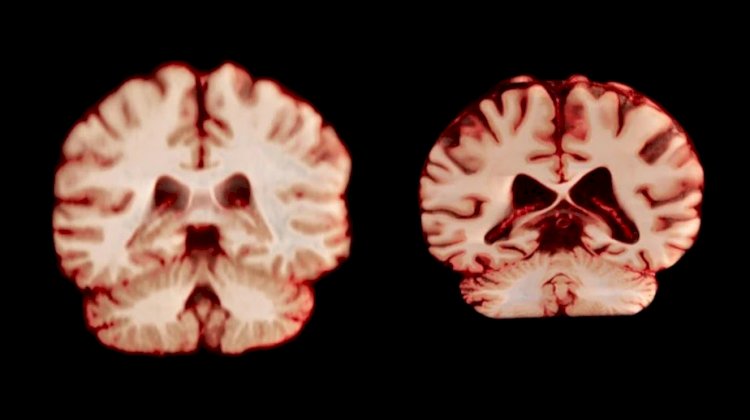

O envelhecimento traz inevitáveis mudanças para o cérebro humano, entre elas, a perda de massa cinzenta e a redução de volume em diversas regiões. No entanto, o ritmo dessa transformação pode variar entre os sexos. Um novo estudo sugere que os cérebros masculinos encolhem mais rapidamente do que os femininos, e mais áreas são afetadas nesse processo.

A pesquisa é uma das mais abrangentes já realizadas sobre o tema. Ela reuniu mais de 12,5 mil exames de ressonância magnética de 4.726 pessoas, todas sem Alzheimer ou qualquer comprometimento cognitivo. Cada participante passou por pelo menos dois exames, com um intervalo médio de três anos – o que permitiu observar as transformações cerebrais ao longo do tempo.

Os cientistas analisaram a espessura da substância cinzenta e o volume de regiões associadas à memória e à doença de Alzheimer, como o hipocampo e o pré-cúneo. Ao comparar os resultados, constataram que os homens apresentaram uma redução de volume maior e mais generalizada.

Um exemplo marcante é o córtex pós-central, área responsável pelo processamento do tato, da dor e da percepção de movimento. Essa região mostrou um declínio de 2% ao ano nos homens, contra apenas 1,2% ao ano no caso das mulheres.